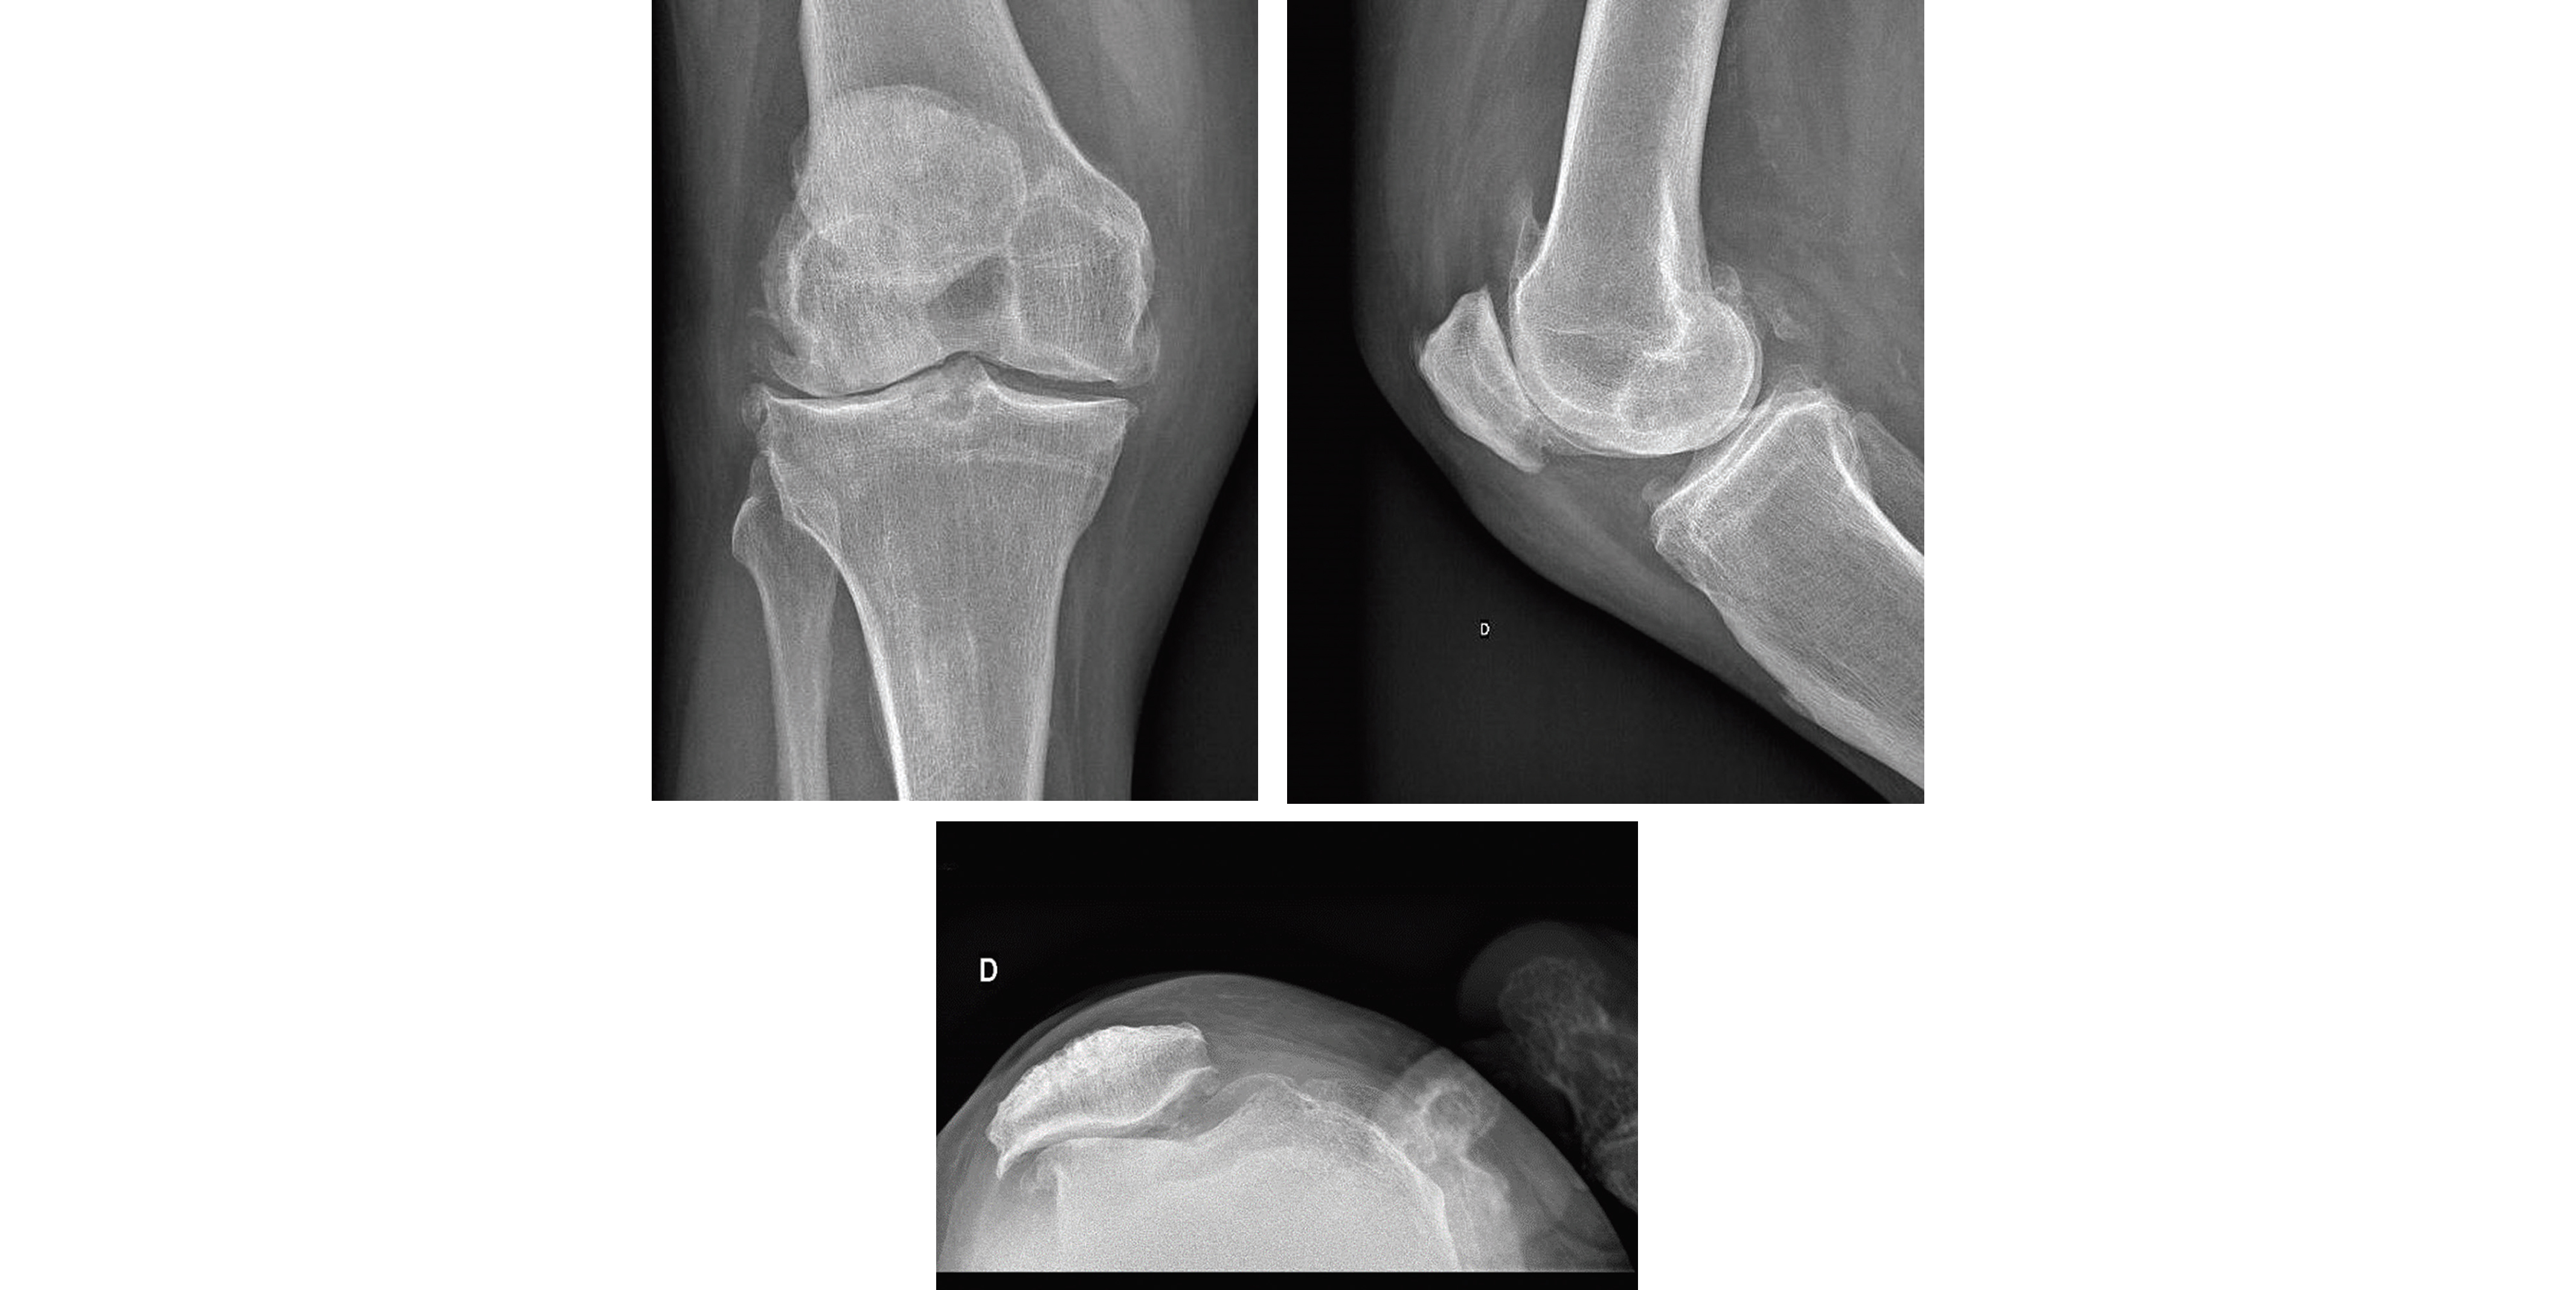

La gonarthrose peut toucher un ou plusieurs compartiments (fémoro-patellaire, fémoro-tibial médial ou fémoro-tibial latéral). La douleur est mécanique à la mise en charge, à la montée et descente des escaliers, à la marche. Mais elle peut aussi évoluer par poussées congestives avec alors une douleur continue et un épanchement articulaire.

L'examen clinique va rechercher une déformation en genu valgum ou genu varum, un épanchement articulaire avec la présence d'un choc rotulien et du signe du flot, un kyste poplité dans le creux poplité et va mesurer les amplitudes articulaires. L'examen doit être déforréalisé de façon bilatéral et comparatif. La perte du recurvatum physiologique peut s'observer assez tôt mais l'installation d'un flessum s'observe dans les formes évoluées. La douleur à la palpation des interlignes fémoro-tibiales médiale et latérale permet d'orienter ver l'attente d'un ou de plusieurs compartiments, et les signes de Zohlen et du Rabot recherchent une atteinte fémoro-patellaire.

Le diagnostic est confirmé par la radiographie des genoux bilatérale en charge de face, de profil, en schuss et avec un défilé fémoro-patellaire à 30° sur laquelle on retrouvera les signes caractéristiques de l'arthrose.

Radiographie d'une gonarthrose tricompartimentale de genou droit chez un patient de 75 ans, clichés de profil

(en haut à droite), déflilé fémoro-patellaire (à gauche), et de face (en bas à droite).